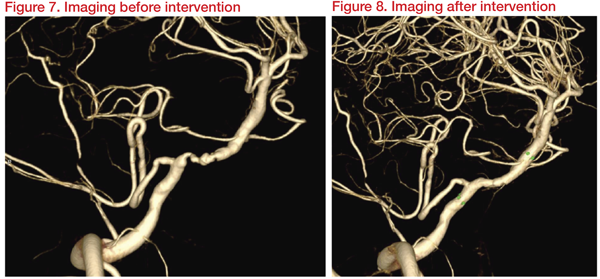

Medication with dual antiplatelet treatment (DAPT) and percutaneous transluminal angioplasty (PTA) with intracranial stenting was planned. Three weeks after DAPT, imaging results revealed a Type II proatlantal intersegmental artery (PIA) with 66 percent stenosis at right vertebral artery (VA, V4 segment) distal to posterior inferior cerebellar artery (PICA). Hypoplasia of left vertebrobasilar junction and occlusion of left VA with plaque was observed.

Angioplasty and stenting were carried out with Gateway 3*15mm and Wingspan 4*20mm. This achieved dilatation of right VA (PIA) from 1.2 mm to 2.4 mm and restoration of basilar flow. At discharge, clinical muscle power improved, and 10 months later, NIHSS and mRS improved to 13 and 3, respectively.